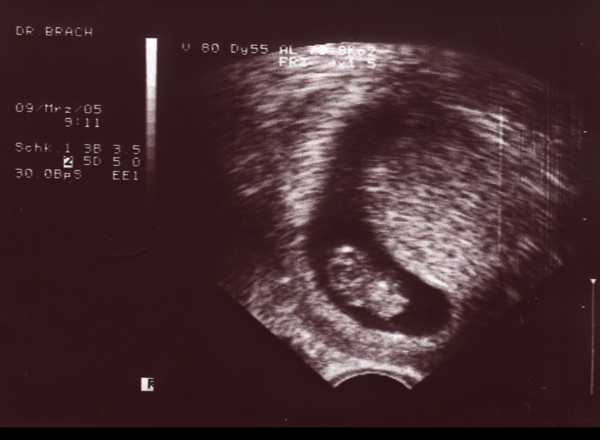

09.05.05 - 10. Woche - 2,0cm